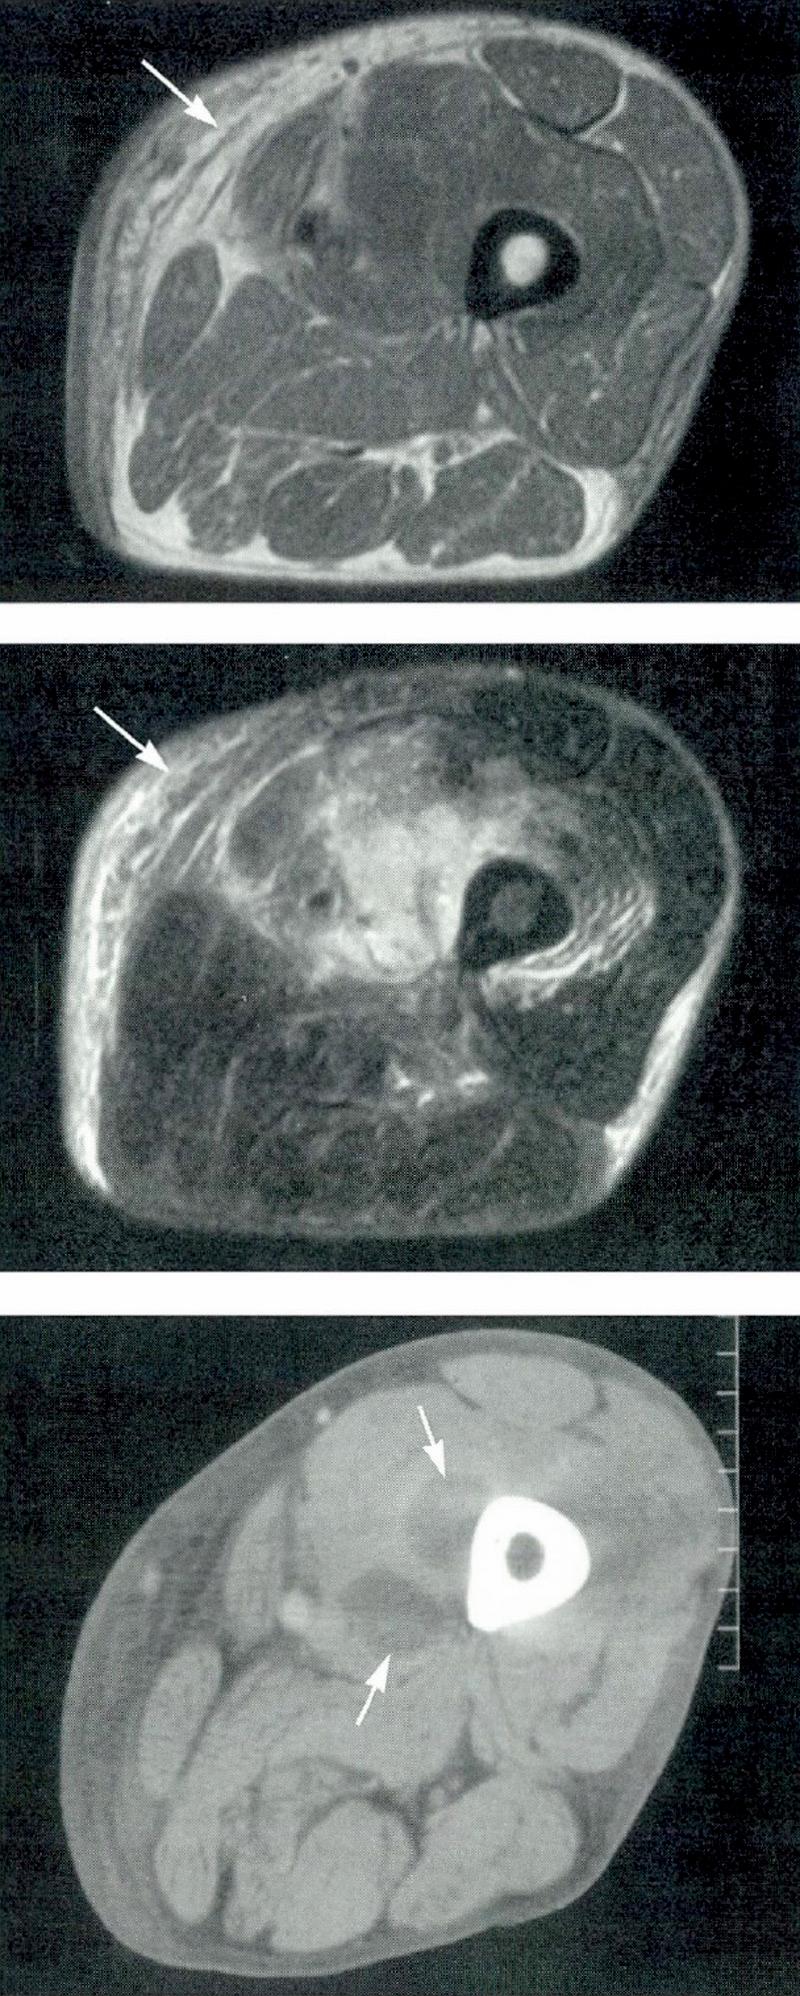

Healthcare providers use an MRI — images of the inside of your body — to diagnose pyomyositis. They might also use blood tests or a bacterial culture to look for an infection.